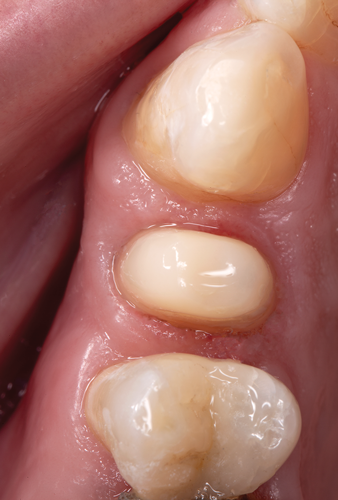

After completion of the endodontic treatment and crown lengthening to develop an ideal ferrule effect (Figure 3 through Figure 5) a diagnostic wax-up was fabricated to an ideal coronal preparation geometric shape, dimension, and height for the anticipated final composite core buildup (Figure 6). A clear polyvinyl siloxane (PVS) impression material was injected into a nonperforated tray, placed over the diagnostic wax-up, and then put into a pressure pot with cold water for 5 minutes. This procedure is aimed at reducing the potential for the formation of voids and bubbles in the impression material (Figure 7 and Figure 8). A small opening was made above the tooth to be restored using a tapered diamond bur (6847) (Figure 9). It is important to clean the internal surfaces with a microbrush to prevent silicone debris from integrating into the flowable material. Prior to the restorative procedure, a diagnostic wax-up was fabricated to the anticipated extracoronal contours for development of the final crown (Figure 10).

Fig 3. After endodontic treatment, crown lengthening was performed to develop an ideal ferrule effect.

Fig 4. An adequate collar effect of 2 mm of sound tooth structure would provide an anti-rotational feature for the stability of the crown.

Fig 5. Buccal view of optimal ferrule effect with a healthy biological framework.